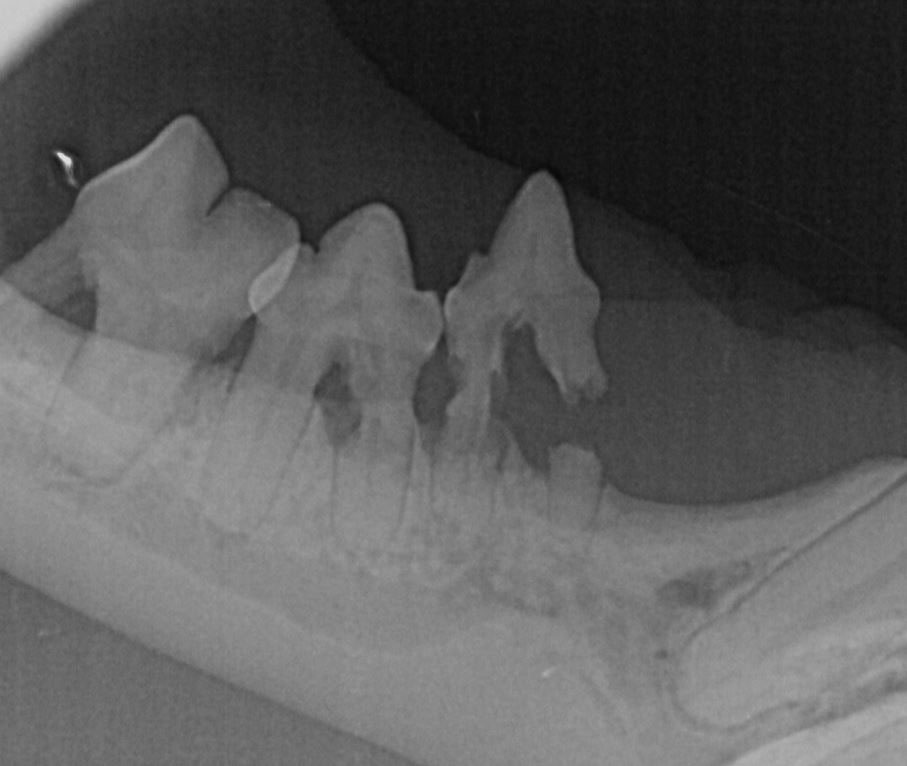

An diesen Stellen ist auch gerötetes Zahnfleisch zu sehen, welches entzündlich verändert ist und sich teilweise über die Zahnhälse schiebt.. Es empfiehlt sich daher aufgrund des sehr häufigen Auftretens der FORL bei der Katze ab einem Alter von fünf Jahren regelmäßig Röntgenaufnahmen anzufertigen. So kann eine beginnende Erkrankung.. Zahnprobleme der Katze sind im Wesentlichen geprägt durch zwei Erkrankungen, die überdurchschnittlich häufig bei Katzen anzutreffen sind. Resorptive Läsionen (FORL) Chronische Gingivitis / Stomatitis. Die Erkrankung “Resorptive Läsionen” (FORL) wird fälschlicherweise häufig als Zahnhalskaries oder Neck Lesions bezeichnet.

Forl Katze Röntgenbild information online

FORL (Feline odontoklastische resorptive Läsion) ist eine Autoimmunerkrankung, bei der sich die Zähne und die Zahnwurzeln der betroffenen Katzen von innen heraus auflösen. Der Zahnerkrankung FORL bei Katzen lässt sich weder vorbeugen noch ist die Zahnkrankheit heilbar. Ab dem fünften Lebensjahr erkrankt jede zweite Katze an FORL.. Die Abkürzung FORL stammt von der Bezeichnung „Feline Odontoklastische Resorptive Läsionen” (Englisch: Feline Odontoclastic Resorptive Lesions) ab. Es handelt sich um eine häufig bei Katzen vorkommende degenerative Zahnkrankheit, die zu sehr schmerzhaften Löchern in den Zähnen führt. Manche bezeichnen die FORL auch als „Resorptive.